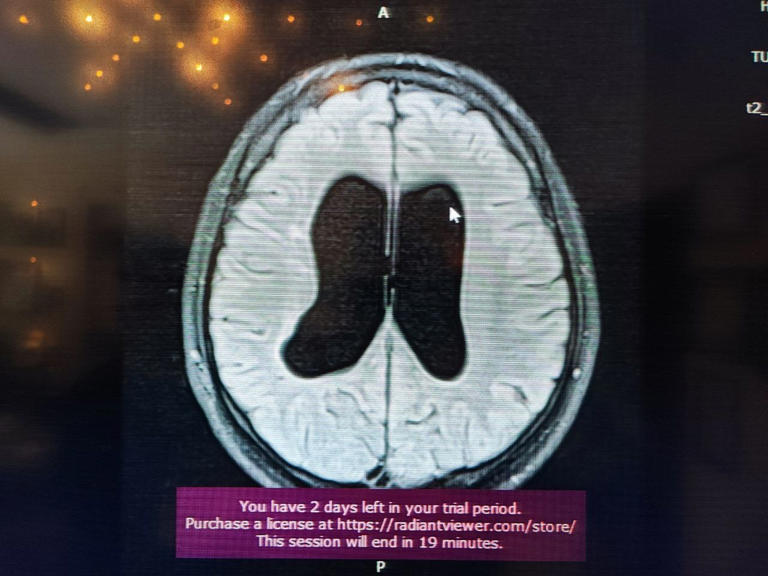

Süreçle ilgili bilgi veren Beyin, Sinir ve Omurilik Cerrahisi Uzmanı Prof. Dr. Orhan Şen, "17 yıl önce, 10 günlük bebekken annesi ve dedesi tarafından bana getirildi. Doğar doğmaz doktorlar ameliyat önermişler. Hidrosefali nedeniyle beyinde su toplanması var, bu nedenle acil ameliyat etmemiz gerekiyor yoksa ölür demişler. Gaziantep ve Adana’da farklı yerlere götürmüşler. Genel olarak hep ameliyat demişler. Ben muayenesini yaptım ve bıngıldak denilen yere baktığımda normal bombelikteydi. Anneye sordum, normal dururken kusma var mı? diye. ‘Hayır, yemek yerken kusma oluyor’ dedi. Muayeneye devam ettiğimde çocuğun klinik tablosu, nörolojik muayenesi ve filmi birbiriyle uyumlu değildi. Bunun üzerine acil ameliyat gerekmiyor, izleyelim. dedim. Bıngıldakta bombe olursa ve arka arkaya kusma olursa o zaman ameliyatını yaparız dedim. Normalde ilk anne karnındayken gelişen süreçte olan bir olay. Radyolojik olarak çocuğun doğar doğmaz bu bulguyu görmemiz, hepsinin aktif hidrosefali olduğu anlamına gelmiyor. Bazen yeni doğanlarda olan ufak kanamalardan kaynaklanabiliyor" dedi.

Sözlerini sürdüren Prof.Dr. Şen "Bizim çocuğumuzda, anne karnında yaşanan bir süreç olduğu için beyine ekstra bir baskı uygulamıyordu. Beyin buna göre gelişmişti. Anne, bizim söylediğimizi tercih etti. O tercihin üzerine şu an 17 yıl geçti. 17 yaşında ve ilkokul ile ortaokulu birinciliklerle tamamlayan genç, şimdi de üniversiteye hazırlanıyor. Bizim burada asıl amacımız, özellikle genç meslektaşlarıma sesleniyorum: Hidrosefali tanısı konulan her çocuk acil ameliyatlık değildir. Bazen arrest hidrosefali olabilir ve şant takmak gerekmiyor. İzlemekte fayda var. Her müdahale cerrahi müdahale değildir. Doğruyu söyleyip göstermek en güzel müdahaledir" diye konuştu.